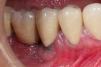

PeriodontitisProgresión de la inflamación gingival (fig. 1) que afecta a las estructuras de soporte del diente. Inicialmente asintomática, su avance supone la destrucción de las estructuras que fijan el diente, pérdida de hueso maxilar y, finalmente, la caída de la pieza dental. Afecta al 30% de los adultos2.